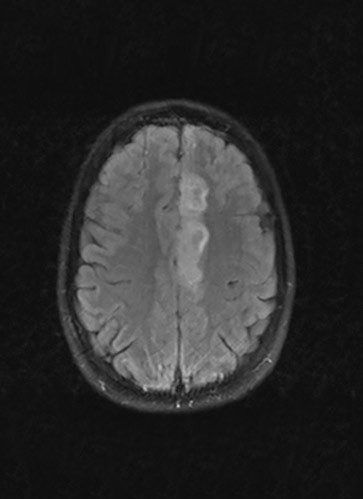

Cerebral MR dagen etter innkomst (bildet til venstre) viste infarktforandringer i mediale deler av venstre frontallapp, svarende til forsyningsområdet til venstre a. cerebri anterior, og MR-TOF-angiografi viste noe trombosering i A2-segmentet av arterien. Pasienten gjennomgikk omfattende utredning uten at man fant noen bakenforliggende årsak til infarktet. Etter to uker ble hun undersøkt med konvensjonell cerebral angiografi, som avdekket en disseksjon i A2-segmentet av venstre a. cerebri anterior (bildet til høyre). En måned senere var hun tilbake i full jobb, da var NIHSS-skår 0 (National Institute of Health Stoke Scale) og modified Rankin Scale (mRS) også 0.